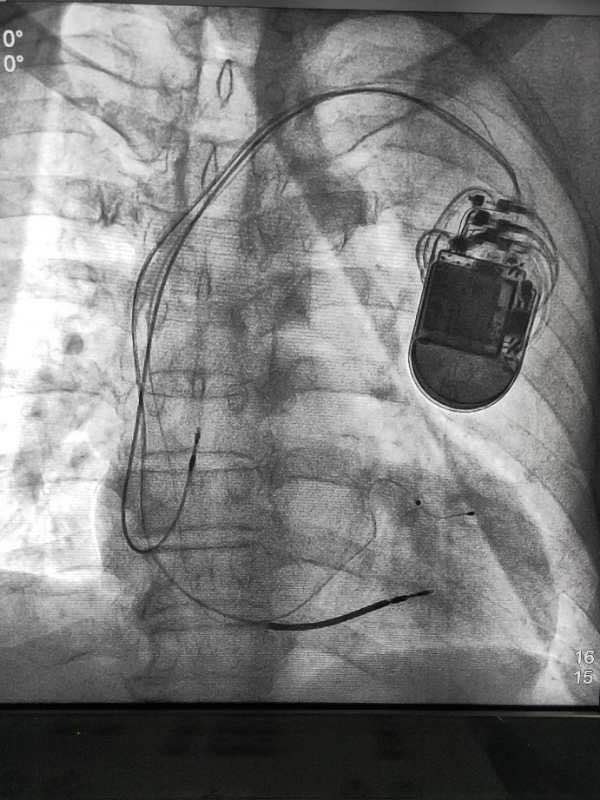

武大爷年龄大,病种多,病情危重,易猝死,如何同时解决他心脏传导阻滞心衰,预防猝死是个非常棘手的问题。在药物治疗基础上,心内科科主任王瑞利决定择期为其行植入心脏再同步复律除颤器(CRT-D)植入术。经过精心准备,住院第3天进行CRT-D植入手术,2小时后顺利植入机器。在介入中心术后患者自我感觉良好,可平躺入睡,无胸闷,活动。耐力明显改善。心率78次/分,出院前评估显示各心电图QRS波变窄,彩超,心脏功能明显改善。

专家点评,王瑞利主任介绍,CRT-D全称是植入式心脏再同步复律除颤器,结合了心脏同步治疗起搏器和埋藏式心脏自动除颤器的双重功能,最大的特点是在起搏心脏的同时保持心脏同步收缩,功能衰竭时,可使扩大的心脏缩小,并能有效防止患者猝死,王瑞利主任说,心脏是人体最重要的器官,一旦出现心律失常,甚至停跳,抢救成功可能性极小。对于部分情况严重或接受药物治疗没有明显效果的患者。植入式心脏起搏器是他们最好的护身符。CRT-D植入术目前是心脏介入手术中的巅峰和难点,我院成功开展此项手术,表明我县心脏介入技术跨上一个更高的台阶。

在心肌病患者中不同步的左室激动可增加等容收缩和舒张时间,从而增加二尖瓣关闭不全的持续时间和缩短心室充盈时间,影响降低前负荷。局部心肌功能减退或继发于异常的不成比例的电激动影响收缩的时间顺序会恶化心肌病患者的心肌收缩功能,因为余下的心肌不能提供代偿性增加心肌纤维缩短以维持必要心博出量。目击手术:换 鞋,换衣服,洗手,穿铅衣……,这是手术医院进入介入导管室的准备动作,这时患者已经准备完毕。平躺于导管室导管床,连接了心电监护仪,进行了常规消毒,铺及局部麻醉。手术开始,全副武装医师为患者穿刺左锁骨下静脉三次留置导丝,沿导丝切口皮肤长约5cm至,被囊袋,沿左锁骨下静脉9F撕开鞘管,送冠状窦电极至冠状窦内,沿电极送长鞘至冠状窦,撤出电极送球能治冠状窦开口处。

行冠状窦逆行造影,确定鞘血管后送导丝经靶血管远端,沿导丝送左心室电极到位,固定好测试起博阀值,沿左锁骨下静脉送入8F撕开鞘管,送左心室电极至左心室心尖部固定好,测试感知及起搏阀值。沿左锁骨下静脉送入另8F撕开鞘管,送左心房被动电极至左心平处固定好,测试感知电压,连接起搏器,将起搏器植入囊袋中,心电监护仪提示良好,手术成功。